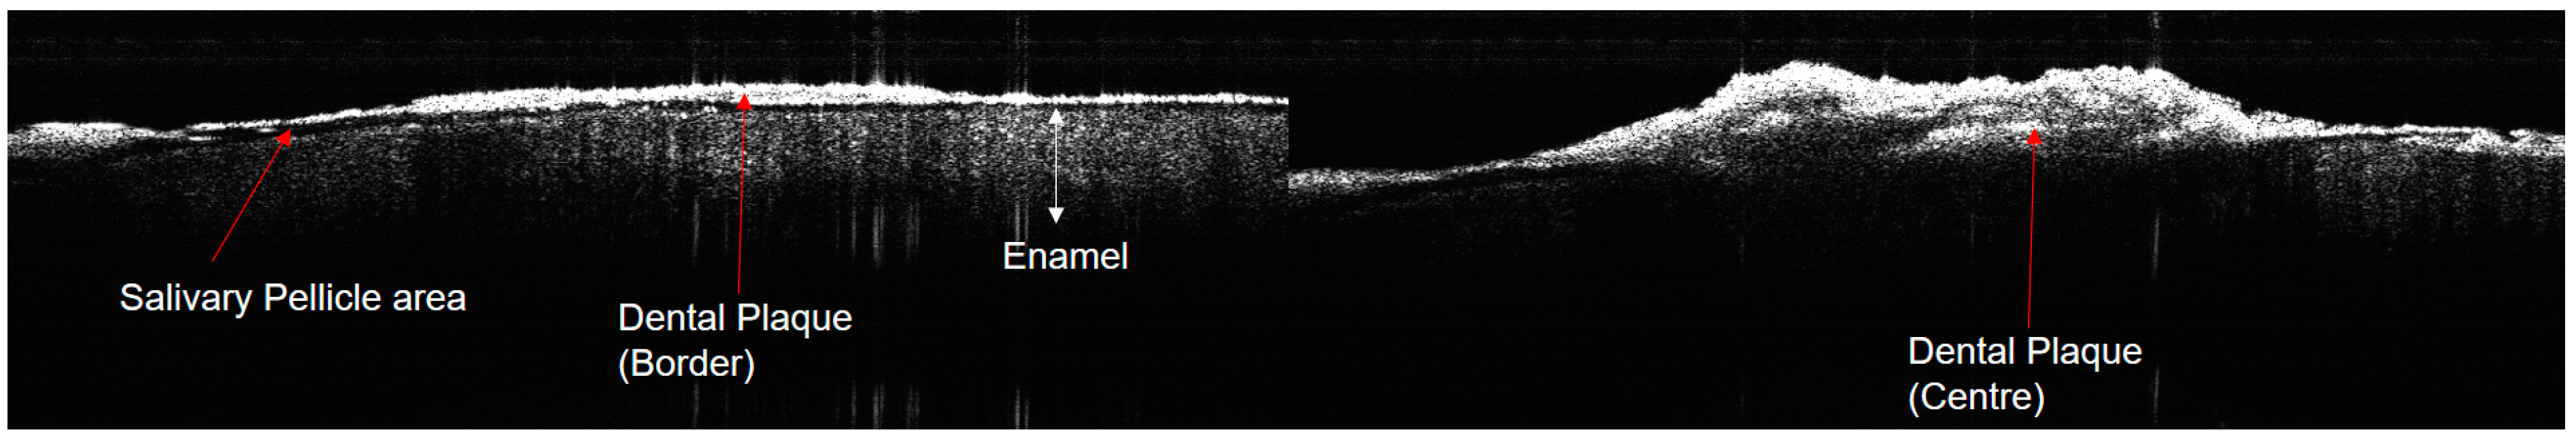

3.3. OCT Imaging of Dental Plaque and Decalcified Area